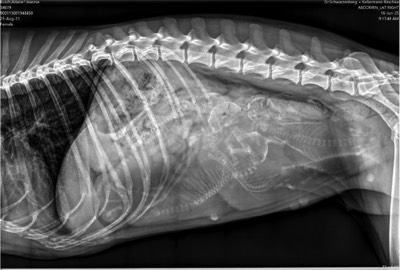

Unsere bezaubernde Jeannie „Tova‘s Riesling Surprise in Germany“ wurde Ende April von unserem charmanten Mio „Golden Nugget's Achilles“ gedeckt.

Wir erhoffen uns von dieser Verpaarung von zwei F3 Windsprites eine Erhöhung der genetischen Diversität mit den damit verbundenen positiven Auswirkungen auf die langfristige Gesundheit der Rasse. Apropos Gesundheit: Jeannie und Mio sind bereits 3,5 und 5,5 Jahre alt. Bis zur Zulassung der F3 Silken Windsprites hat es ja bekanntlich einige Jahre gedauert. Positiv daran ist, dass wir wissen, dass beide Hunde eine phantastische Konstitution und Gesundheit haben. Beide sind körperlich total fit und wirklich robust und unempfindlich – eigentlich waren sie noch nie richtig krank und vertragen jedes Futter.